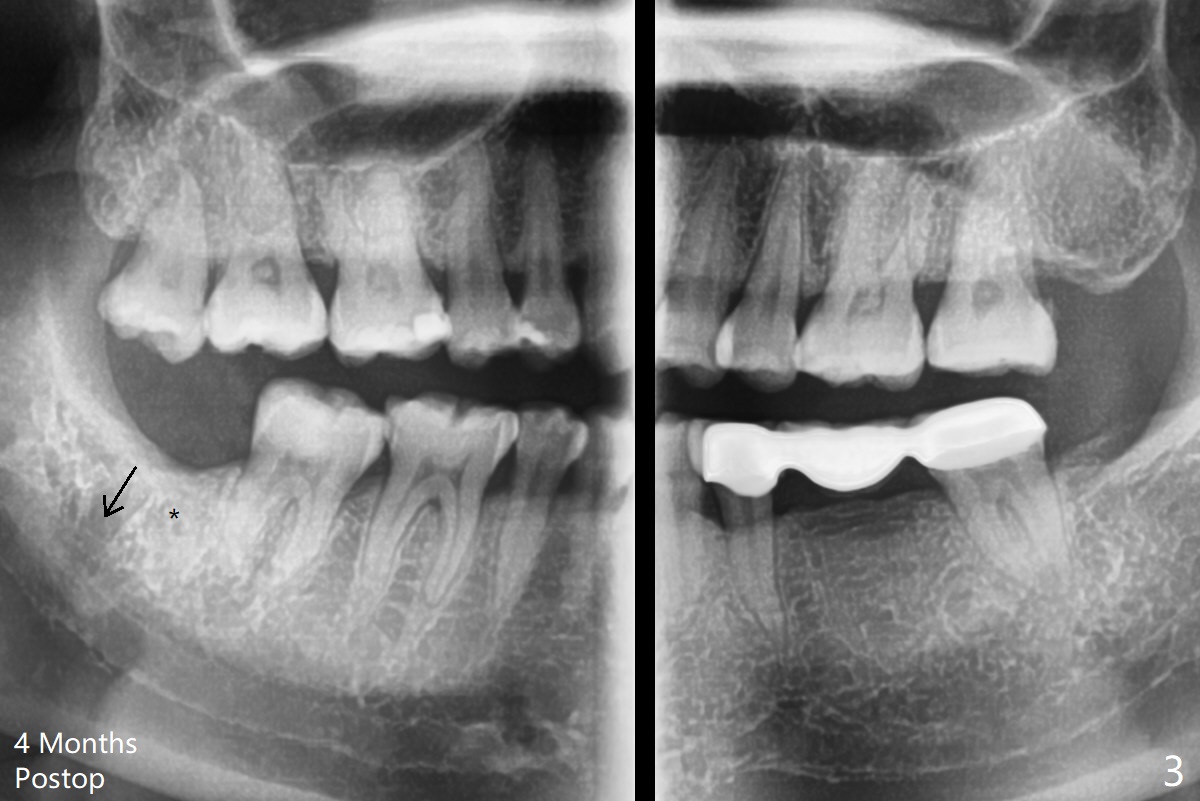

Thin Bone Between 2nd and 3rd Molars M

A 35-year-old woman has pericoronitis distal of #32. The bone between the 2nd and 3rd molars is high, but thin (Fig.1 <). With incision, buccal trough is created at #32 for elevators so that the 2nd molar is not affected by elevation. Collagen plug is placed in the socket to prevent dry socket (Fig.2). The mesial socket is completely ossified (Fig.3 *), while the distal one partially ossified 4 months postop. The ossification in the distal socket seems to be from coronal to apical (Fig.3 arrow), in contrast to the traditional thinking of apico-coronal.